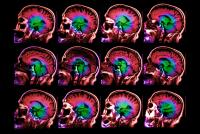

Brain-Aging Gene Discovered

Genetic variant accelerates normal brain aging in older people by up to 12 years

NEW YORK, NY (March 15, 2017)—Columbia University Irving Medical Center (CUIMC) researchers have discovered a common genetic variant that greatly impacts normal brain aging, starting at around age 65, and may modify the risk for neurodegenerative diseases. The findings could point toward a novel biomarker for the evaluation of anti-aging interventions and highlight potential new targets for the prevention or treatment of age-associated brain disorders such as Alzheimer’s disease.